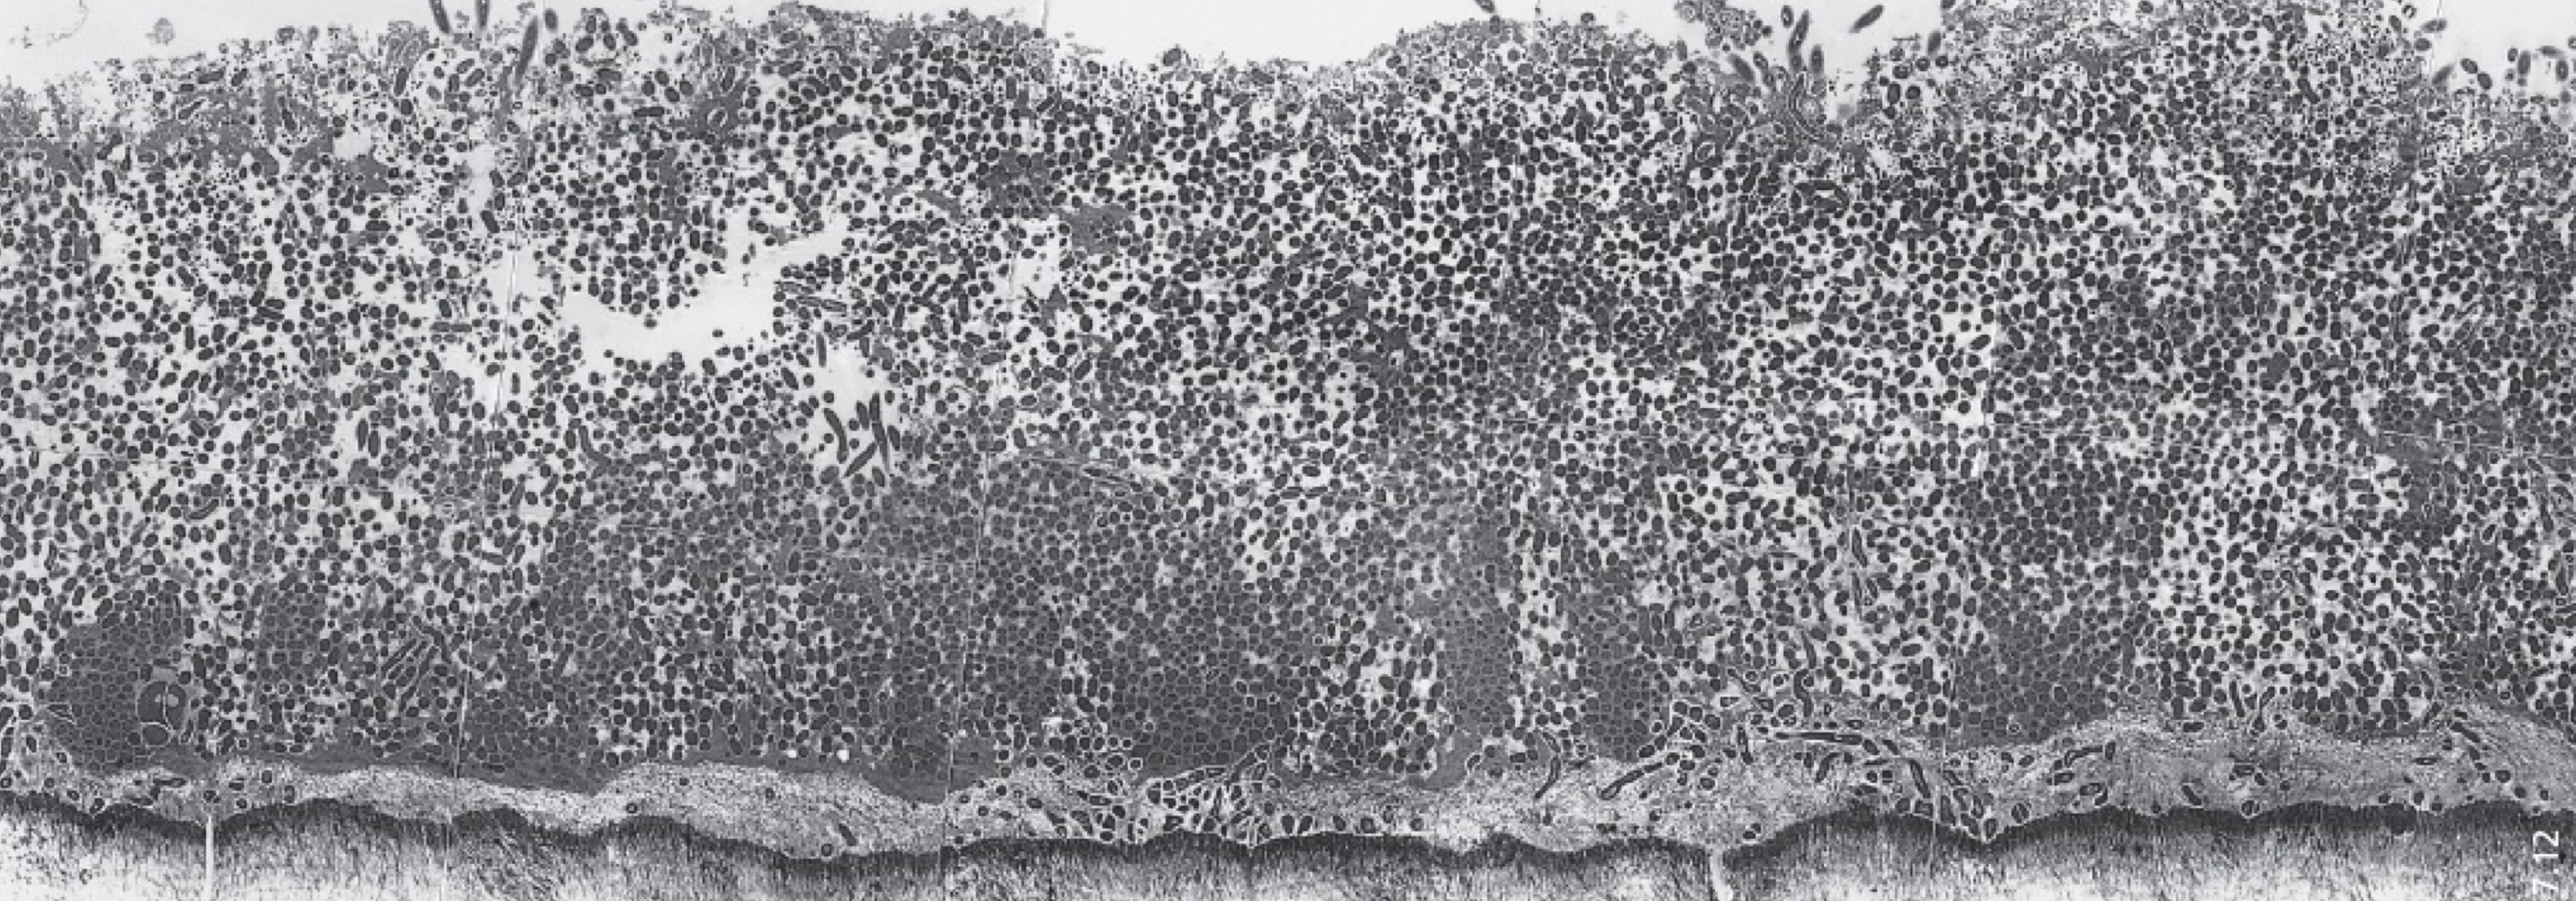

critical pH of enamel

5.5

below this level (more acidic) : minerals dissolve

New cards

critical pH for dentin

5.5 - 7

more alkaline (more basic )

dentin is less calcified, progression of caries is faster

dentinal caries and tubule infection

S. mutans

lactobacillus, actinomyces

bifidobacterium

prevotella

what kinds of dentin are salvageable

demineralized dentin

sclerotic dentin

tertiary dentin

(caries affected (transparent zone))

what kind of dentin is not salvageable

zone of destruction (caries infected, discolored )